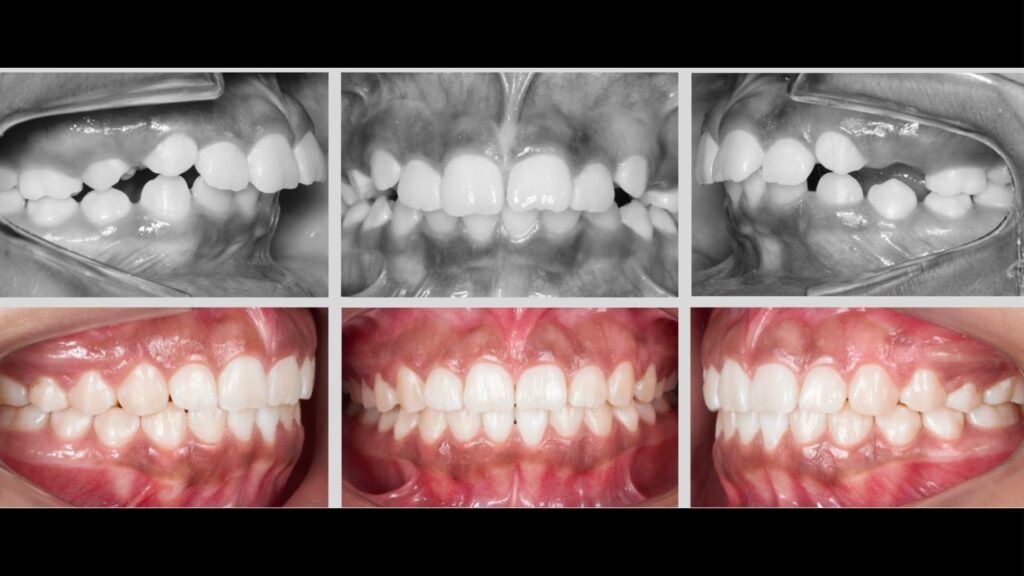

A Ortodontia tem como objetivo corrigir a posição dos ossos maxilares e dos dentes que estão mal posicionados, condição conhecida como má oclusão.

A má oclusão pode afetar os dentes em diferentes direções (vertical, horizontal e transversal). Por isso, o tratamento deve ser feito de forma específica (a arcada é tratada por setores), levando em conta cada caso individualmente. A Ortodontia Bioprogressiva adota esse conceito, tratando os dentes e os segmentos de forma personalizada.

A Ortodontia Bioprogressiva corrige o que está errado sem prejudicar o que já está bom. O diagnóstico vai além do uso de aparelhos. A Bioprogressiva foca nas necessidades específicas de cada paciente, oferecendo um diagnóstico individualizado para um tratamento mais eficaz.